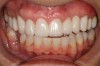

Fig 3. Tooth No. 28 had a Class V filling that failed with recurrent decay (Fig 3). A tuberosity CTG with a 1.5 mm thickness was placed, and after 1 year there was no keloid-like appearance (Fig 4).

Figure 3

Fig 4. Tooth No. 28 had a Class V filling that failed with recurrent decay (Fig 3). A tuberosity CTG with a 1.5 mm thickness was placed, and after 1 year there was no keloid-like appearance (Fig 4).

Figure 4

Class V fillings are artificial materials that tend to fail at the apical extent and have poor long-term success (Figure 3).1 Conversely, CTGs are natural and attach to the root surface and have high long-term success (Figure 4).1

Regarding the avoidance of a gingivoplasty procedure later, there appears to be nothing in the literature describing the ideal thickness of a tuberosity CTG. From palatal and allograft thickness recommendations, one could hypothesize that the thickness be between 0.75 mm and 2 mm. This article will propose a graft thickness between 1 mm to 1.5 mm (Figure 3 and Figure 4) for the optimal functional and esthetic outcome and will discuss various procurement and fileting techniques.

Dense CT presumably is less susceptible to shrinkage than less-dense CT. One problem with denser CT may be the need for a longer amount of time to blend in with adjacent non-grafted areas. Due to density, a CT graft might never completely blend in and always demonstrate an unesthetic keloid-like appearance. Therefore, with tuberosity tissue, adjusting the tissue thickness prior to placement of the graft is highly clinically relevant. This may be why periodontists have been reluctant to use tuberosity tissue as CT. Palatal tissue has less-dense CT than tuberosity tissue and, therefore, the authors hypothesize and have observed, shrinks more. Because palatal tissue has been the predominant tissue used in CTG, clinicians have become used to the shrinkage associated with the palatal CT and may not realize the need to thin a dense CTG to prevent a keloid-like appearance. Thus, in the past when a tuberosity was used for this purpose, if it was not properly trimmed it would have frequently resulted in an unesthetic keloid-like appearance. The tuberosity CTG should be trimmed to 1 mm to 1.5 mm thick to avoid the need for a future procedure to adjust tissue thickness for esthetics (Figure 3 and Figure 4, Figure 16 and Figure 17).